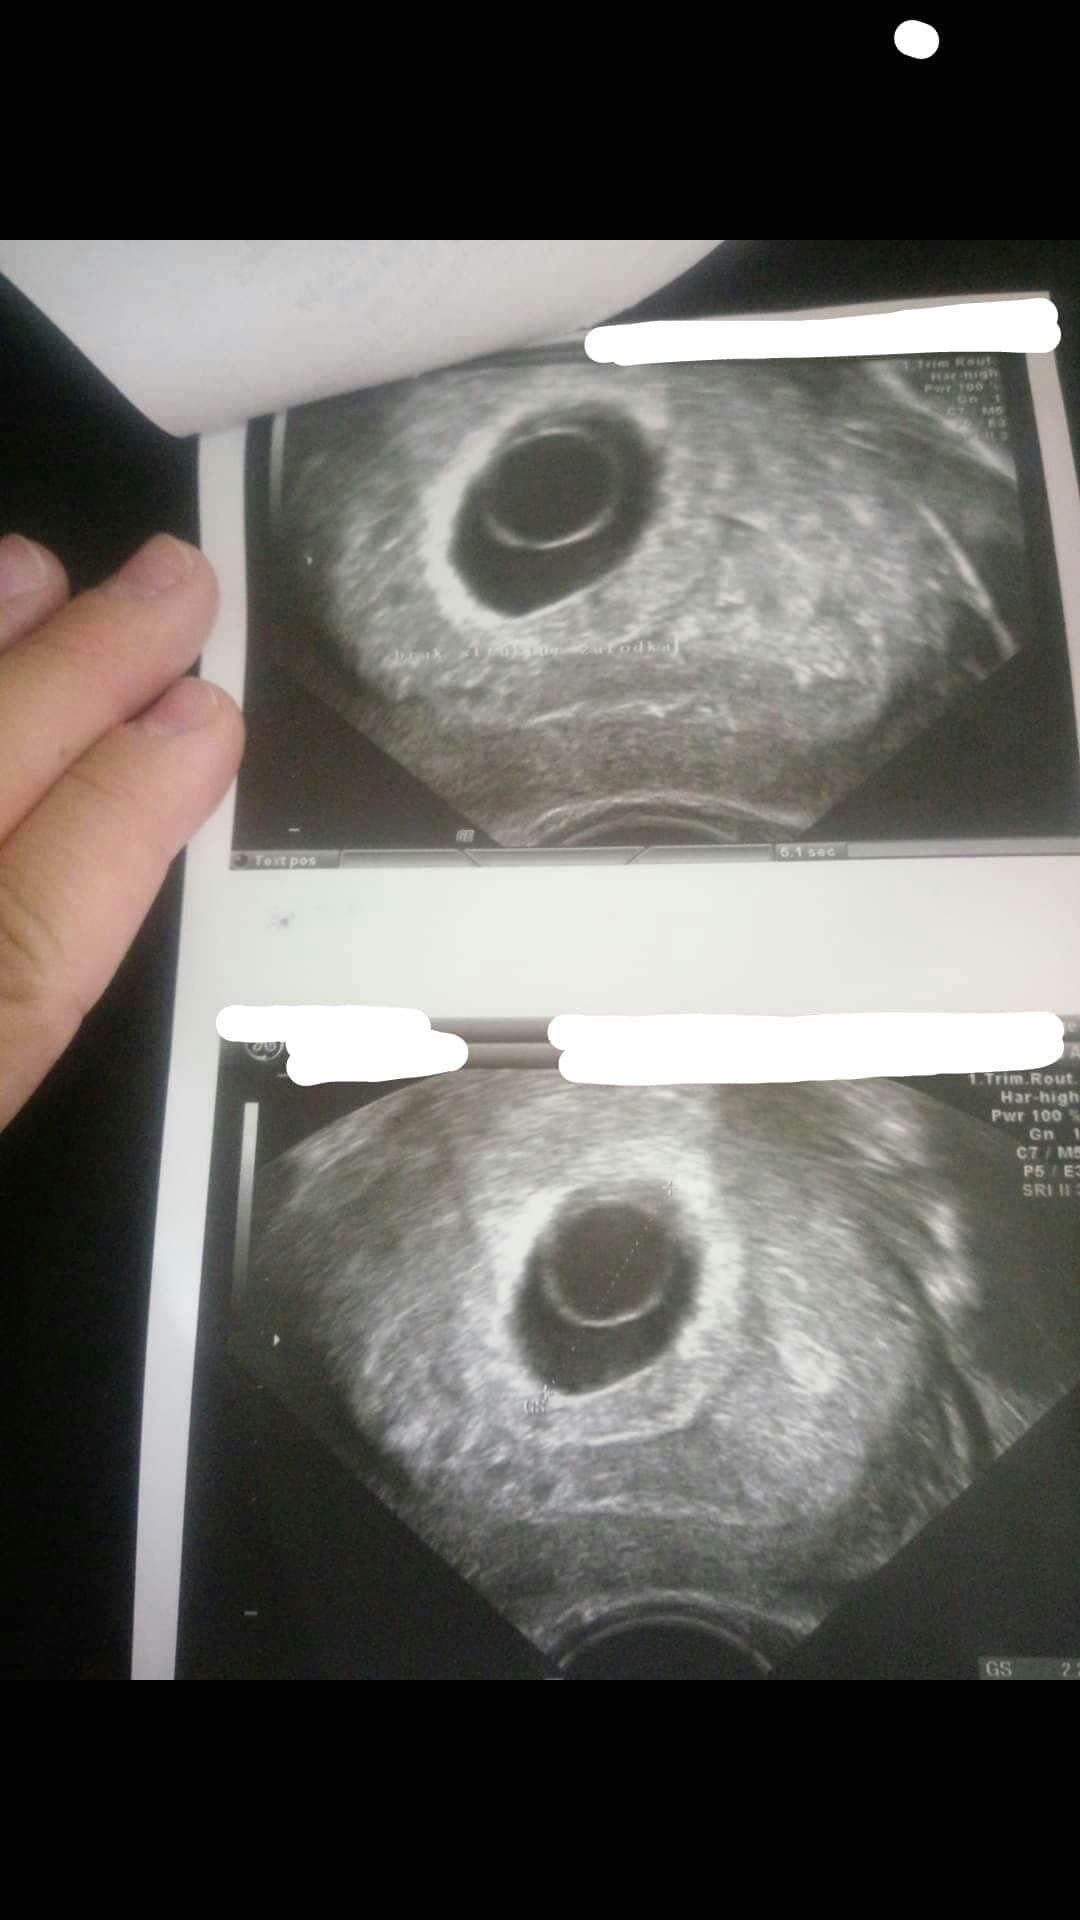

Witajcie dziewczyny. Błagam pomóżcie może któraś miała tak jak ja. 8 lipca (równe 3 tygodnie temu) byłam u ginekologa potwierdzić ciążę- 2 testy pozytywne, brak okresu (ostatnia miesiączka 31.05) z badań krwi wyszło, że jestem w 5 lub 6 tygodniu. Cykle mialam regularne co 22 dni (Tak wiem krótkie ale to norma tak naprawdę). Dzisiaj po 3 tyg udałam się znowu na wizytę kontrolną.. Pan doktor do mnie "To dzisiaj zobaczymy maluszka i posłucham serduszka" ... już po jego minie jak zaczął USG wiedziałam że coś jest nie tak. Brak echa serca, i wciąż tylko pęcherzyk CRL 0.66. Lekarz zaczął mnie uspokajać, że ciąża może być młodsza i mogę być w takim razie w 5 tygodniu a nie w 8-9 jak powinnam... Czy to możliwe? Cykle zawsze miałam regularne co do dnia. Kolejna wizyta za 2 tygodnie ale ja chyba oszaleje do tego czasu.. dodam że nie miałam żadnych objawów poza sennością